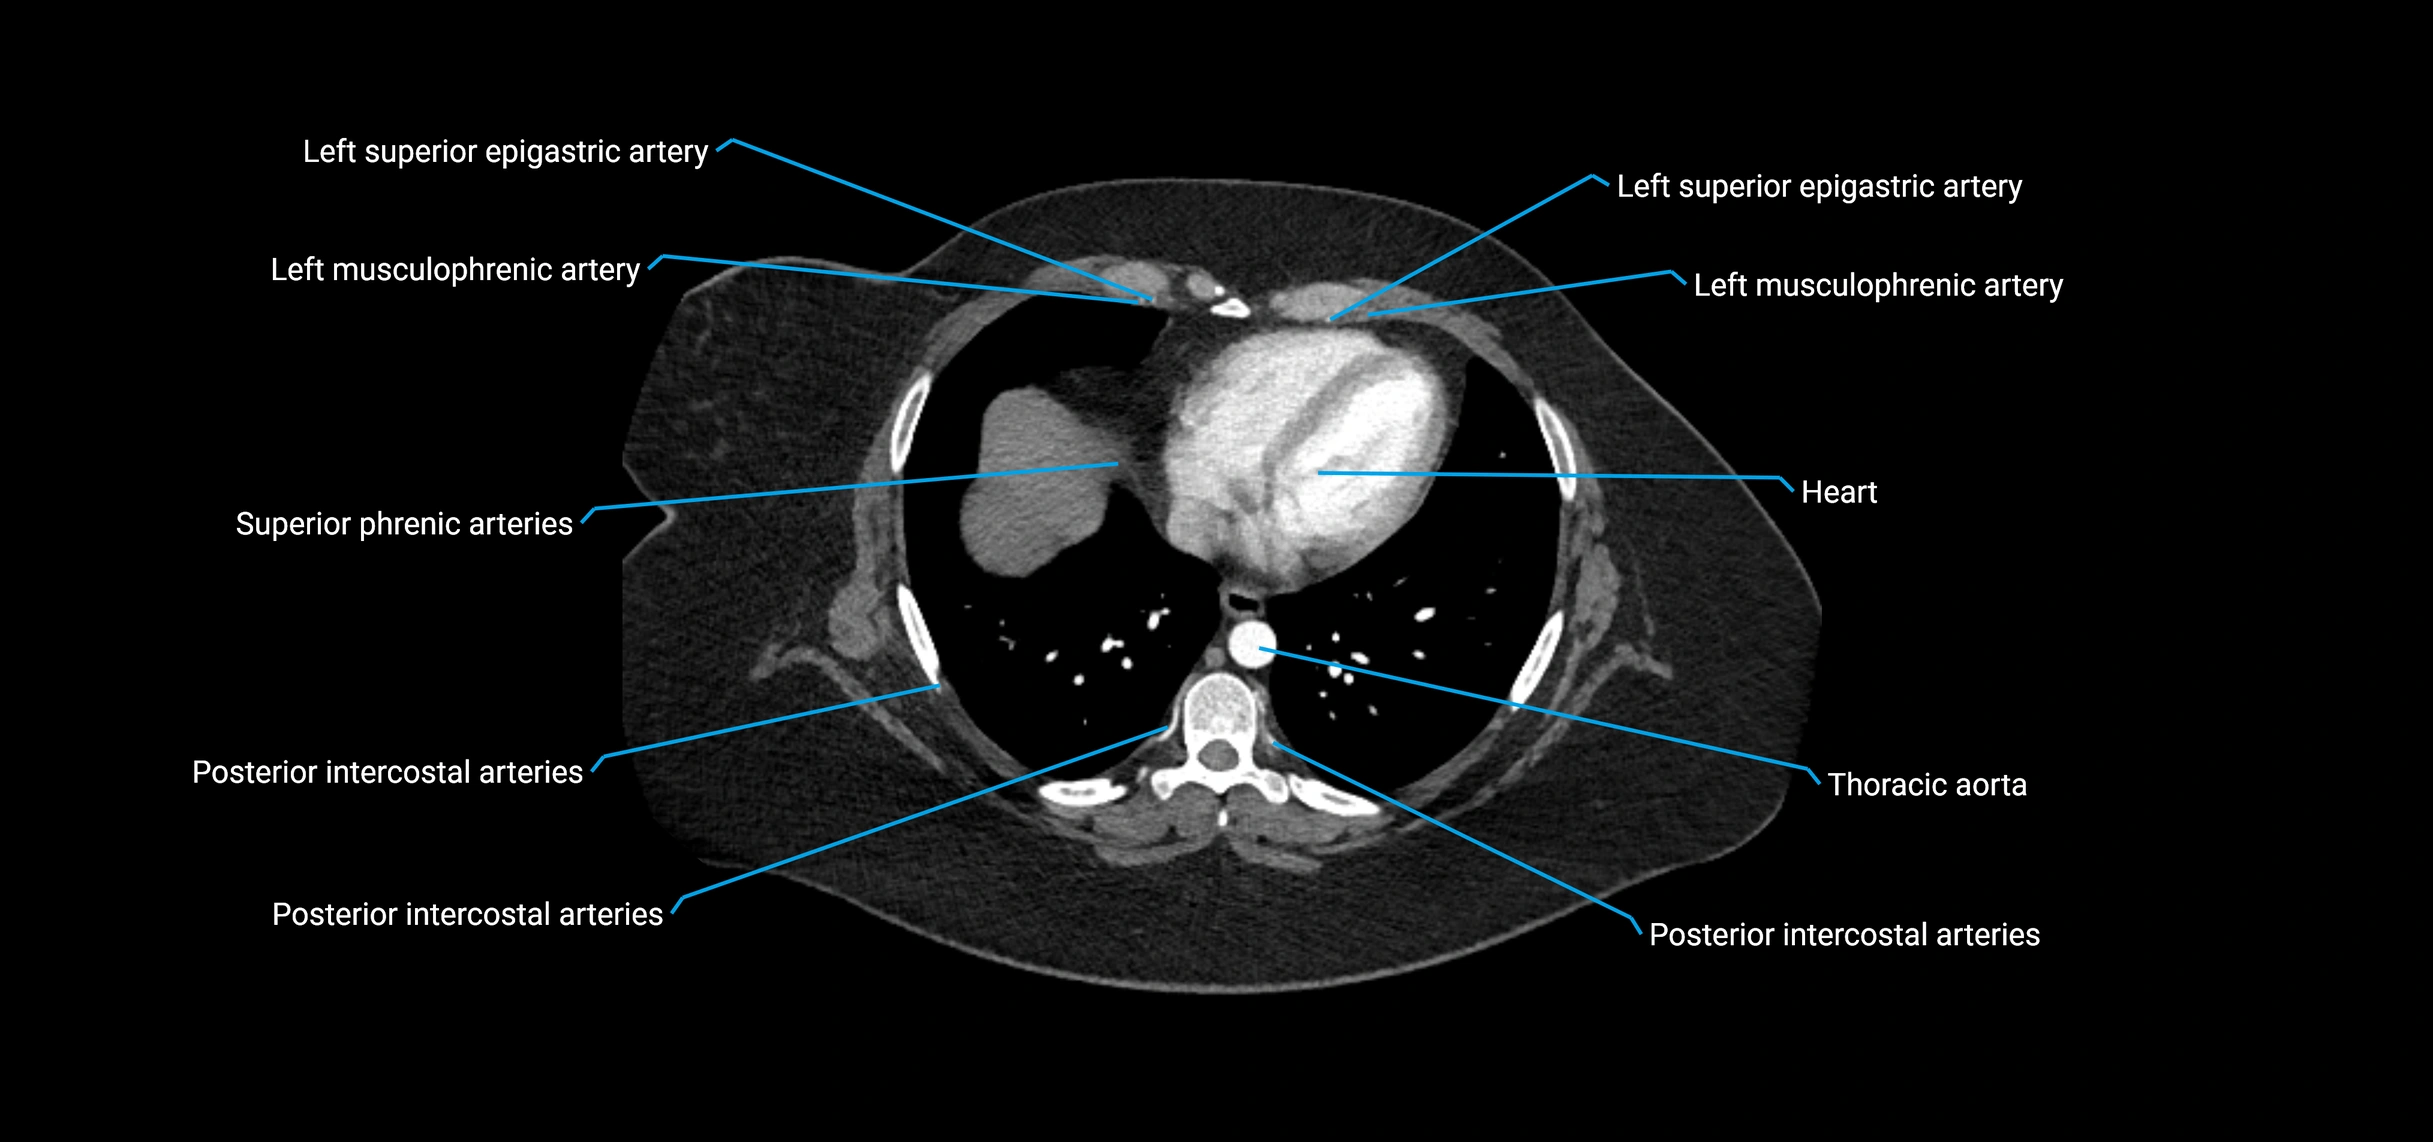

CT images

image